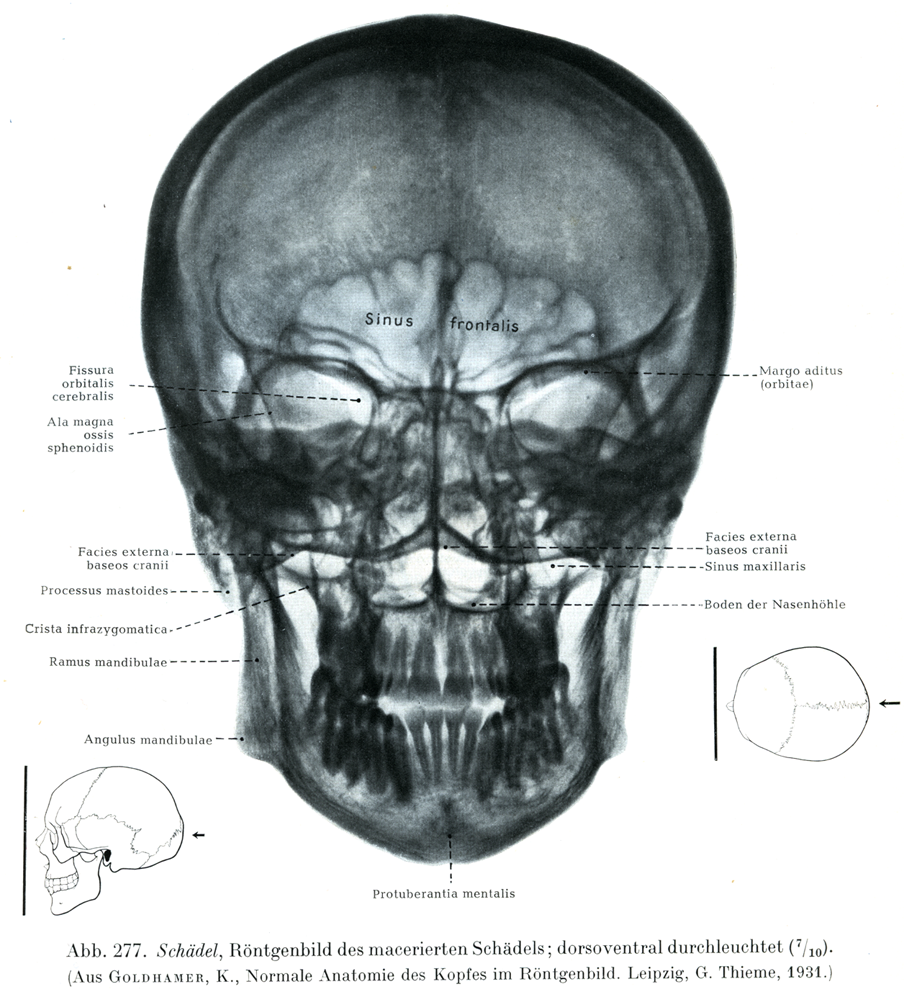

[図277]さらした頭蓋のレントゲン像 背腹照射(7/10)